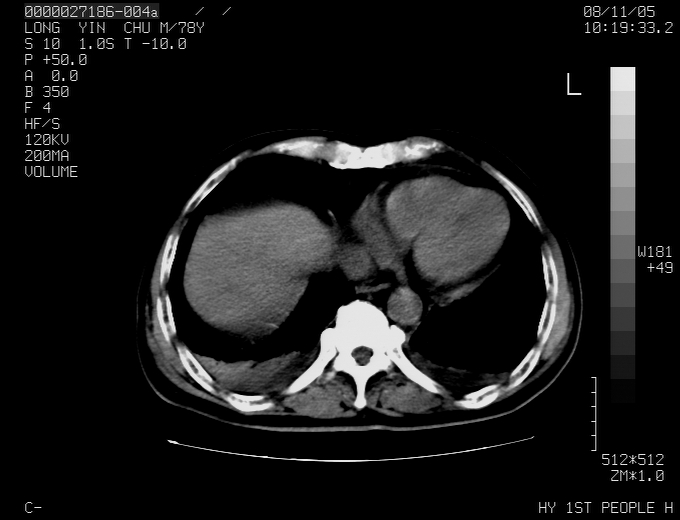

标题: CT16532:M78Y,肝脏病变,请会诊

腹胀,腹痛就诊,男性,78岁,外院b超未见异常。

肝ca,脾肾转移

考虑弥漫性肝癌并脾及双肾转移.双侧胸水.

图片质量欠佳:多考虑:左侧肾癌。脾脏转移!胸膜转移!

肝脾肾转移瘤可能性大,左肾不除外梗塞,双侧胸水